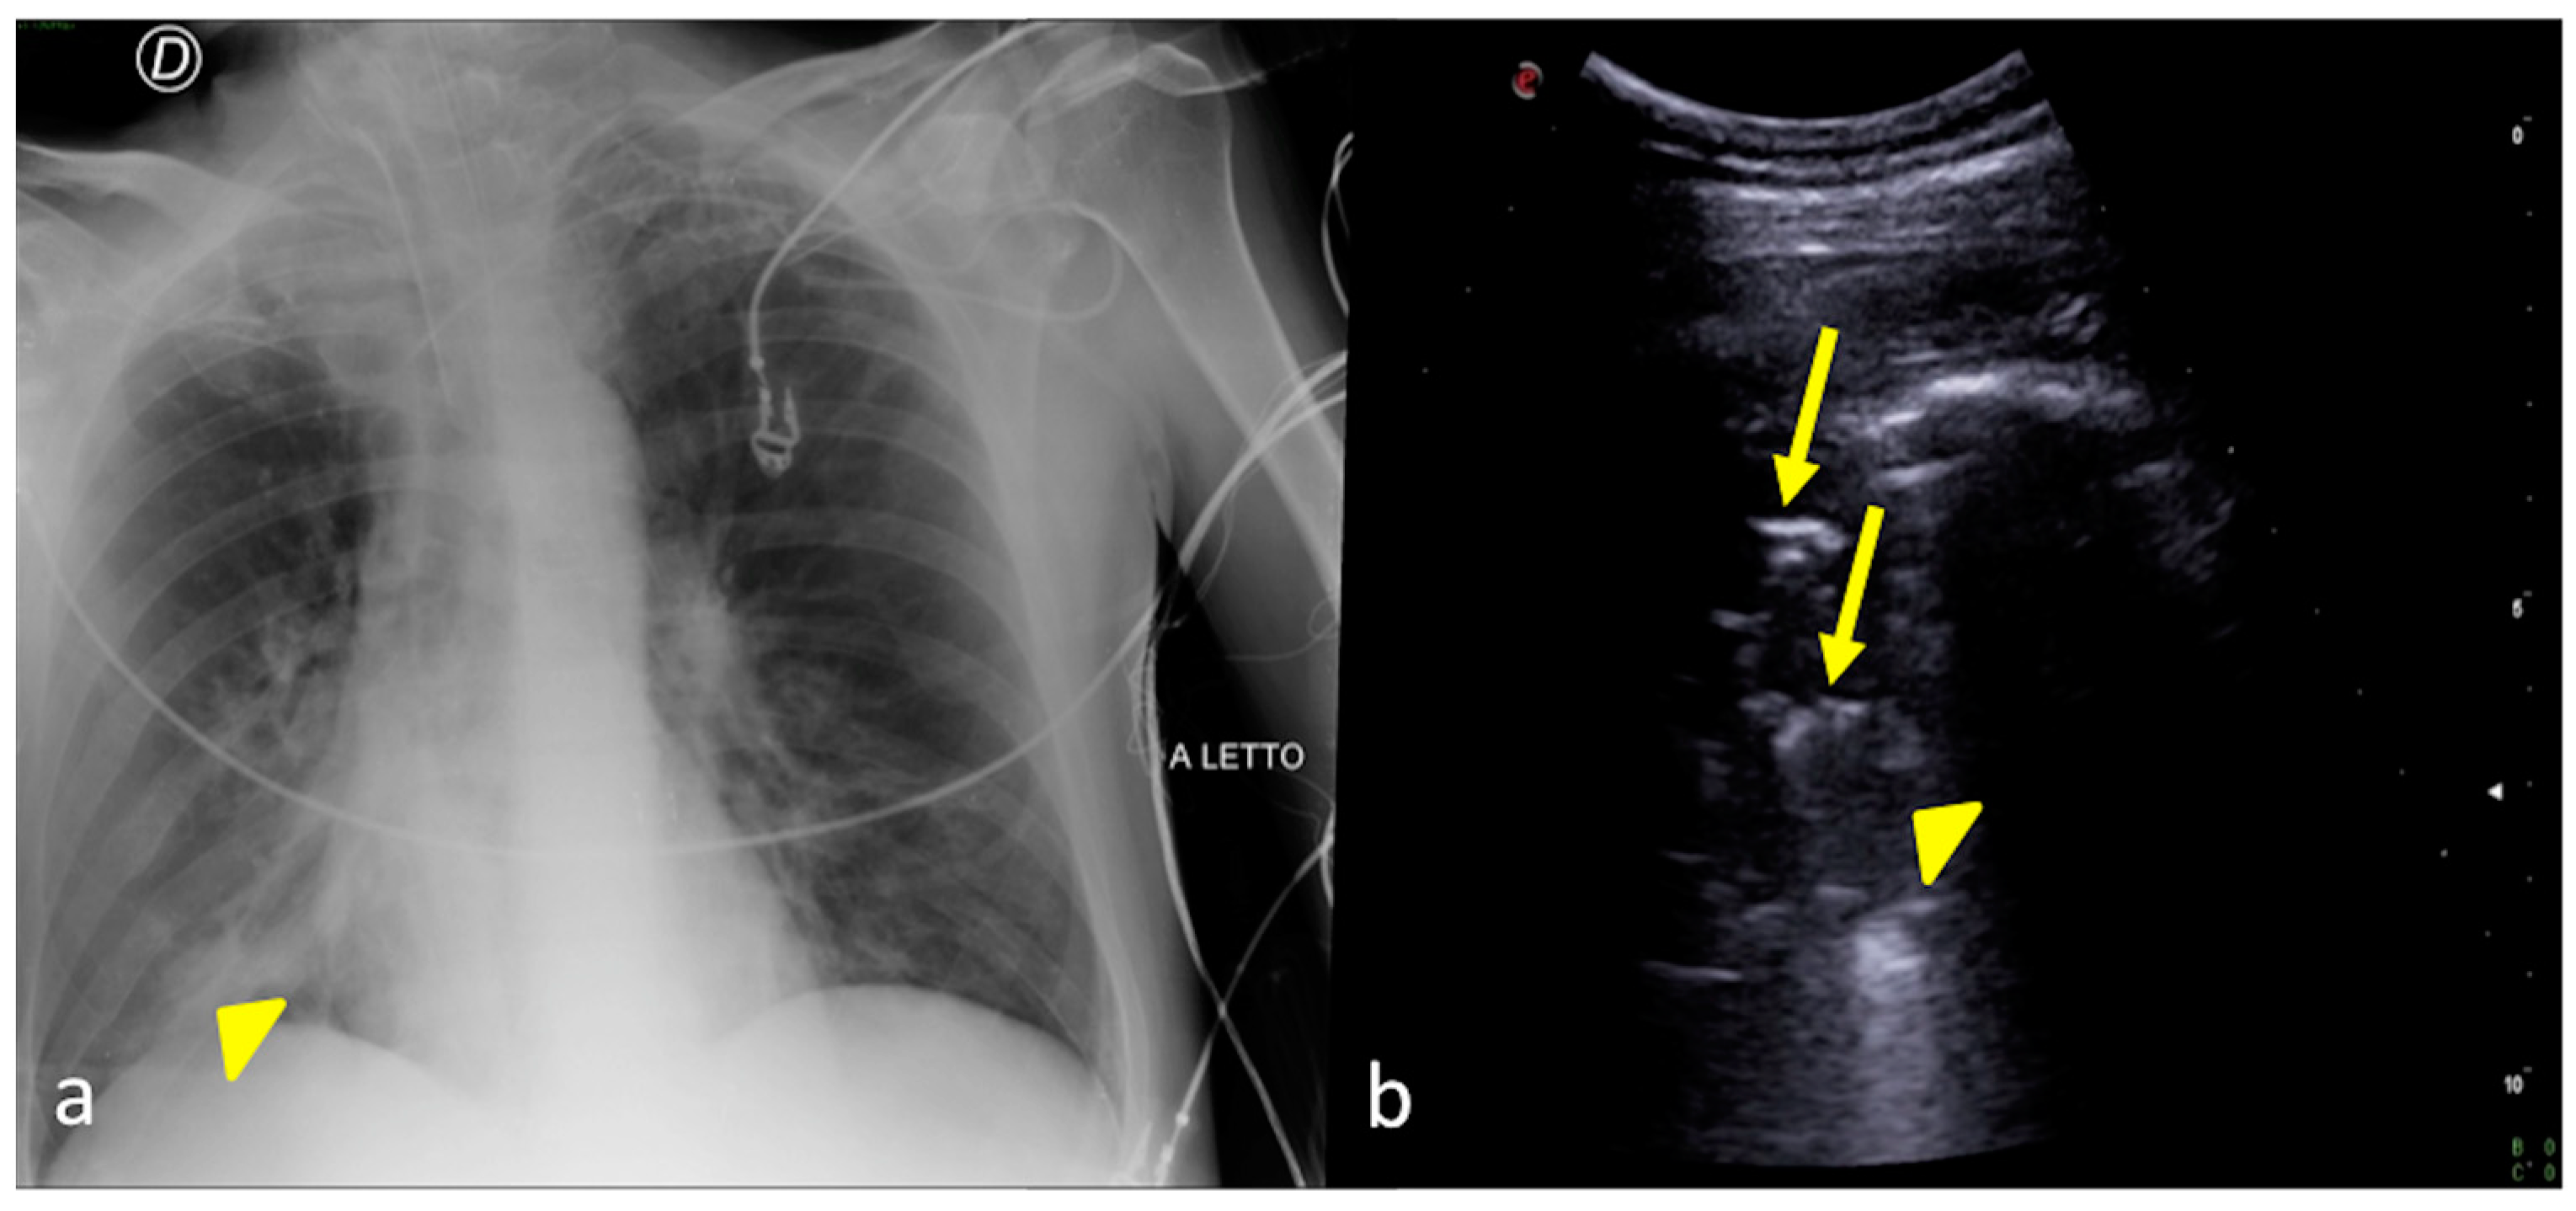

Figure 9.

A 67-year-old male patient referred to the ICU after major trauma by a fall from a height. Bedside CXR (a) and LUS (b,c). (a) The CXR showed bilateral pulmonary opacities associated with pleural effusion (a, arrowheads). (b,c) Bilateral minimal pleural fluid was also confirmed by LUS (b,c, arrows) both on the right (b) and on the left (c) sides; lung consolidation was also visible (b,c, asterisks).